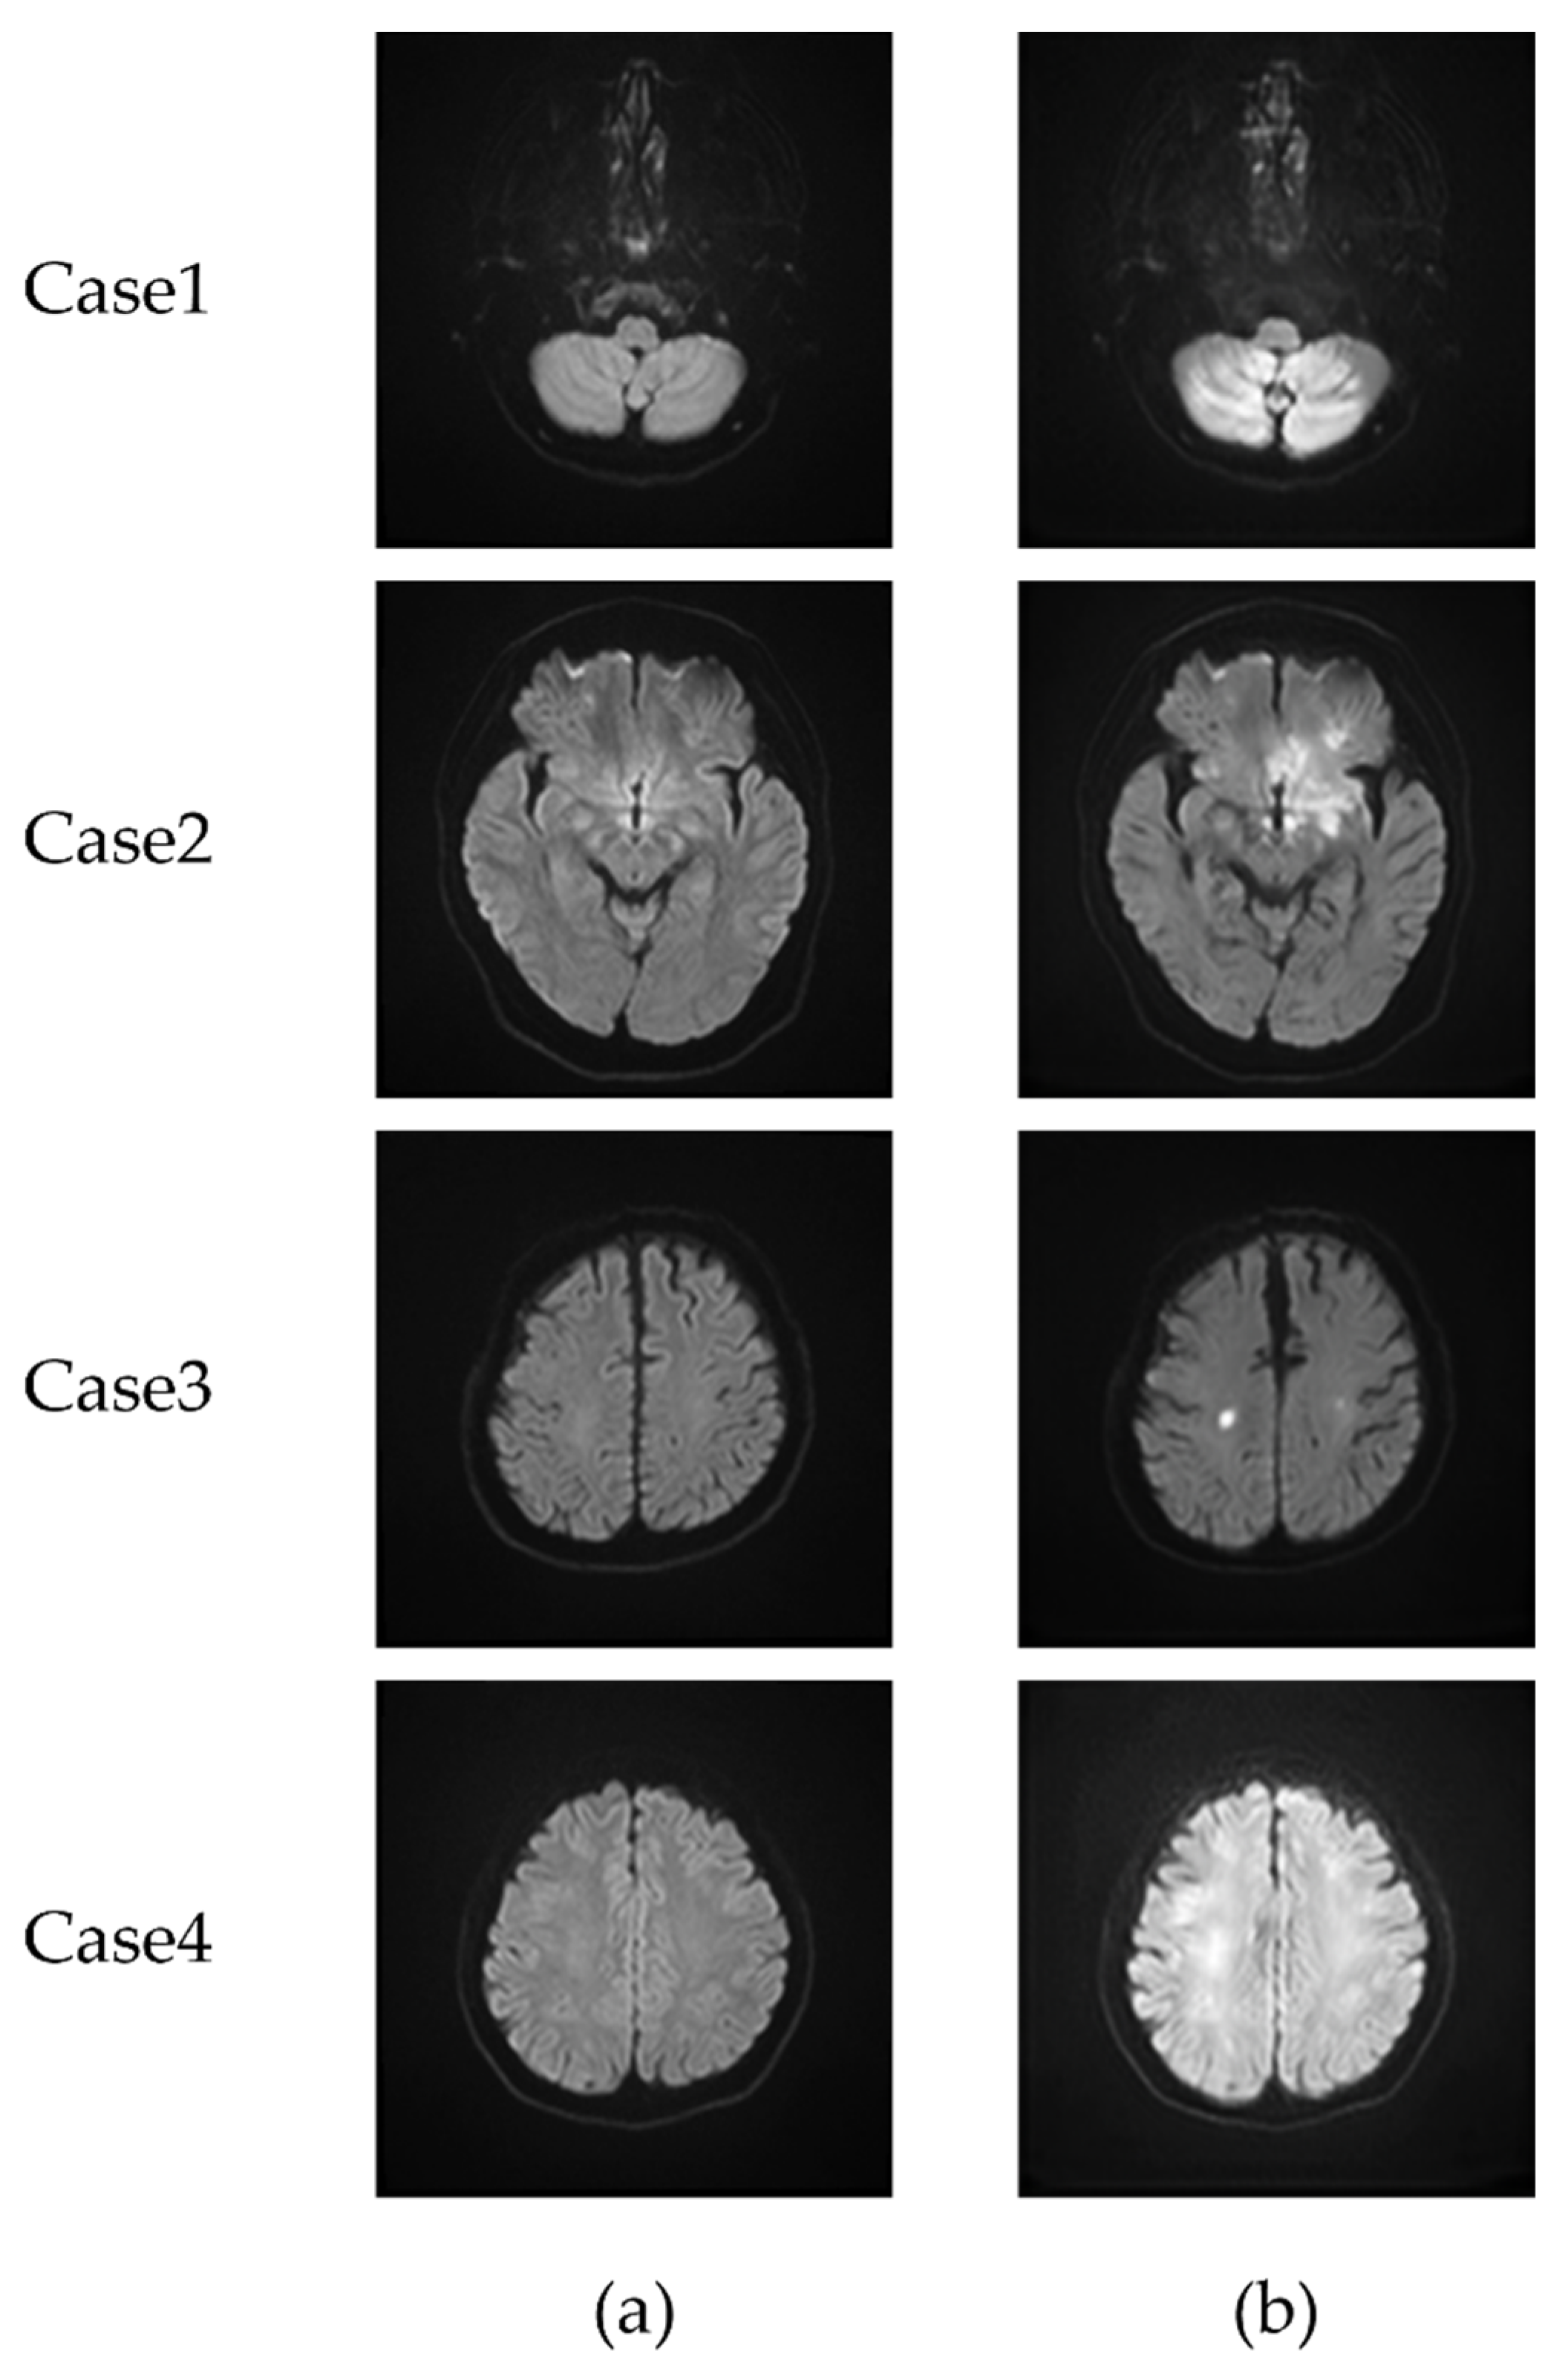

3.1. CycleGAN-Generated Images

3.2. Extraction of the Infarcted Regions